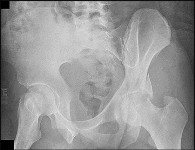

Question 11:

An 18-month-old girl presents with a painless limp and leg length discrepancy. Radiographs show a dislocated left hip with a pseudoacetabulum. What is the most appropriate treatment?

Correct Answer: Open reduction, pelvic osteotomy, and femoral shortening osteotomy

Explanation:

In a walking child over 18 months of age with a completely dislocated hip, open reduction is almost always required. A femoral shortening osteotomy reduces pressure on the cartilage to prevent AVN, and a pelvic osteotomy (e.g., Salter or Pemberton) is usually needed to correct acetabular dysplasia.